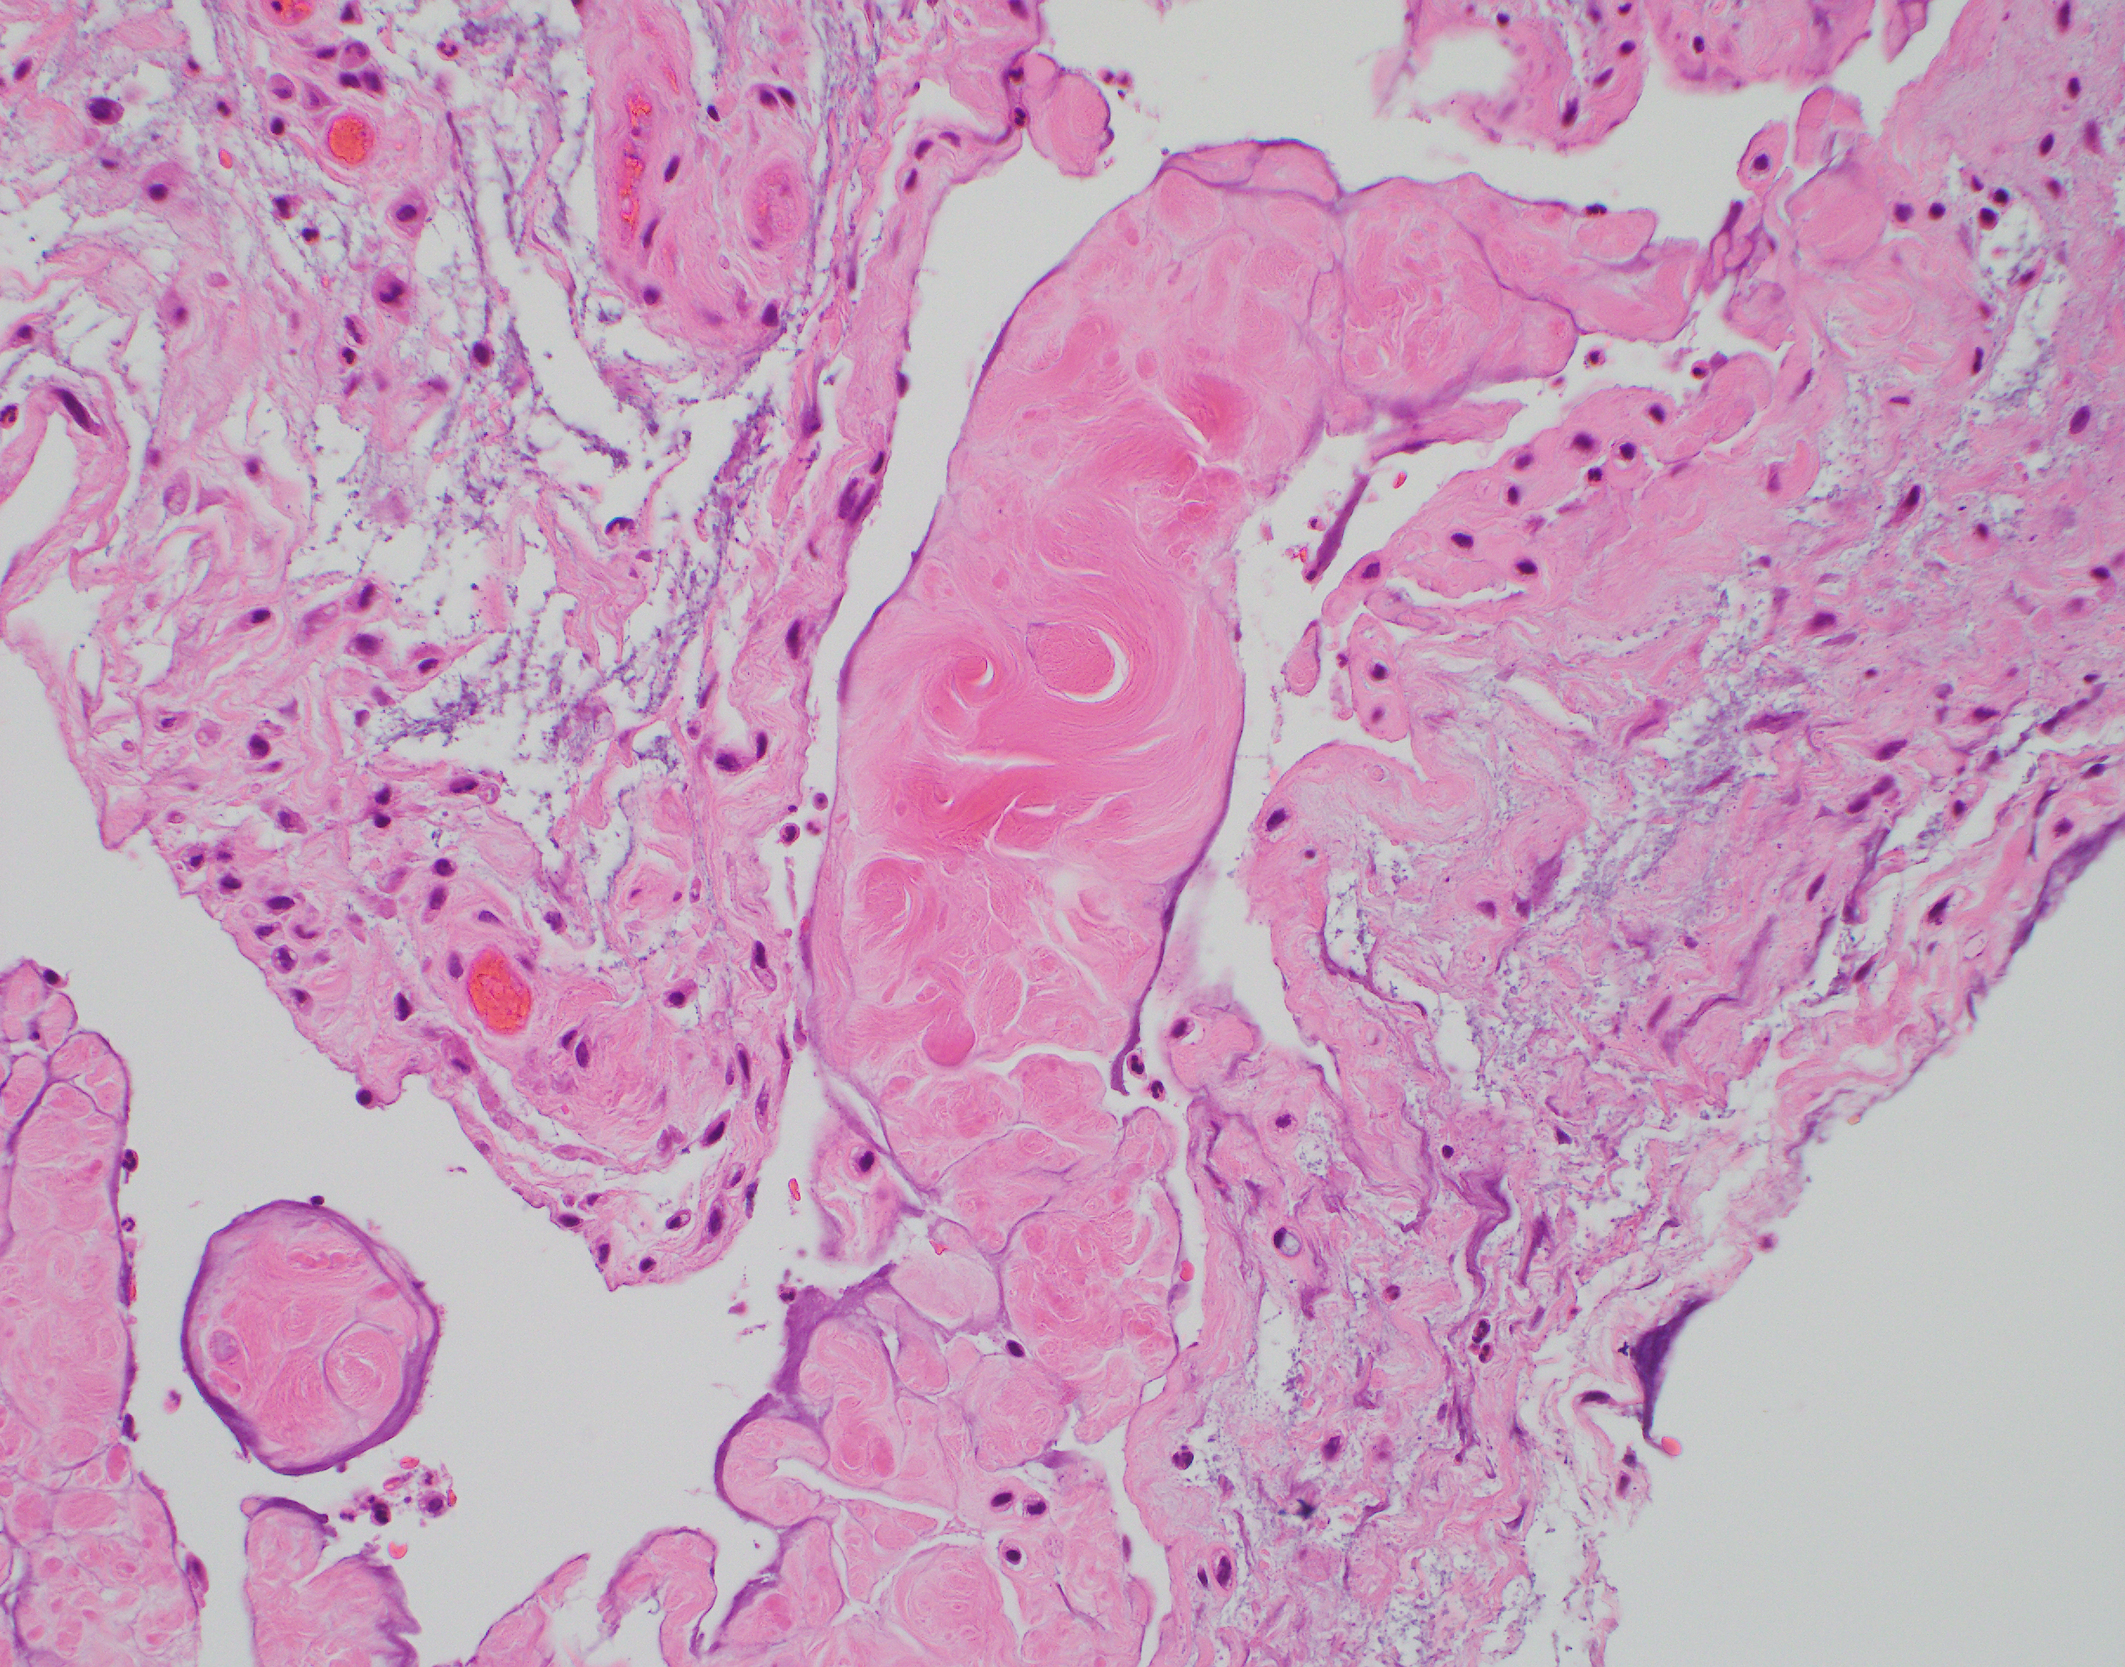

Intraoperative cultures were negative for growth of micro-organisms after five days of incubation and synovial fluid was negative for crystals. Tissue biopsy samples, including median nerve sheath and synovial tissue, sent during surgery, were analysed by immunohistology and Phenol Congo (Congo) red staining. Haematoxylin and eosin (H&E) staining showed a deposit of acellular, eosinophilic, extracellular material characteristic of amyloid (Figure 1). A positive Congo red stain showing red-orange to salmon-pink material highlighted the presence of amyloid as the foci of eosinophilic hyalinisation (Figure 2). When observed under polarised light, the positive Congo red stain demonstrated the ‘apple-green’ birefringence of amyloid (Figure 3).